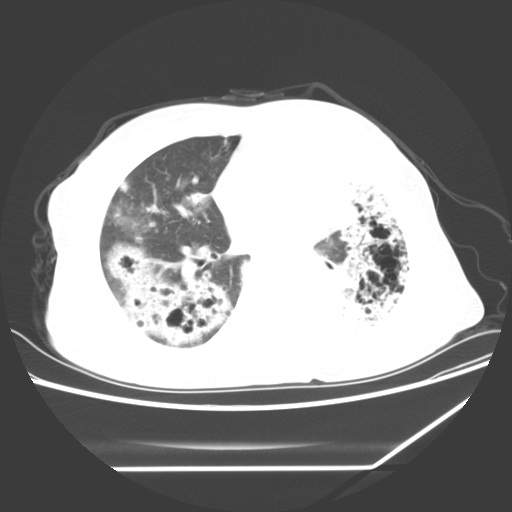

标题: CT25393:病人45岁,咳嗽,吐黄痰带血丝,发热,胸闷月余 [打印本页]

标题: CT25393:病人45岁,咳嗽,吐黄痰带血丝,发热,胸闷月余

1、左肺中央型肺癌并双肺弥漫性转移   2、双肺部感染    3、肺大泡     4、左侧胸腔积液

双侧肺弥漫性病变,可见“空泡征”及“蜂窝征”,考虑肺泡癌可能性大,左侧胸腔积液,考虑胸膜受累可能!

考虑肺泡癌,建议排除感染。

考虑肺泡癌

1)不排除肺泡癌可能。2)左侧胸腔积液。